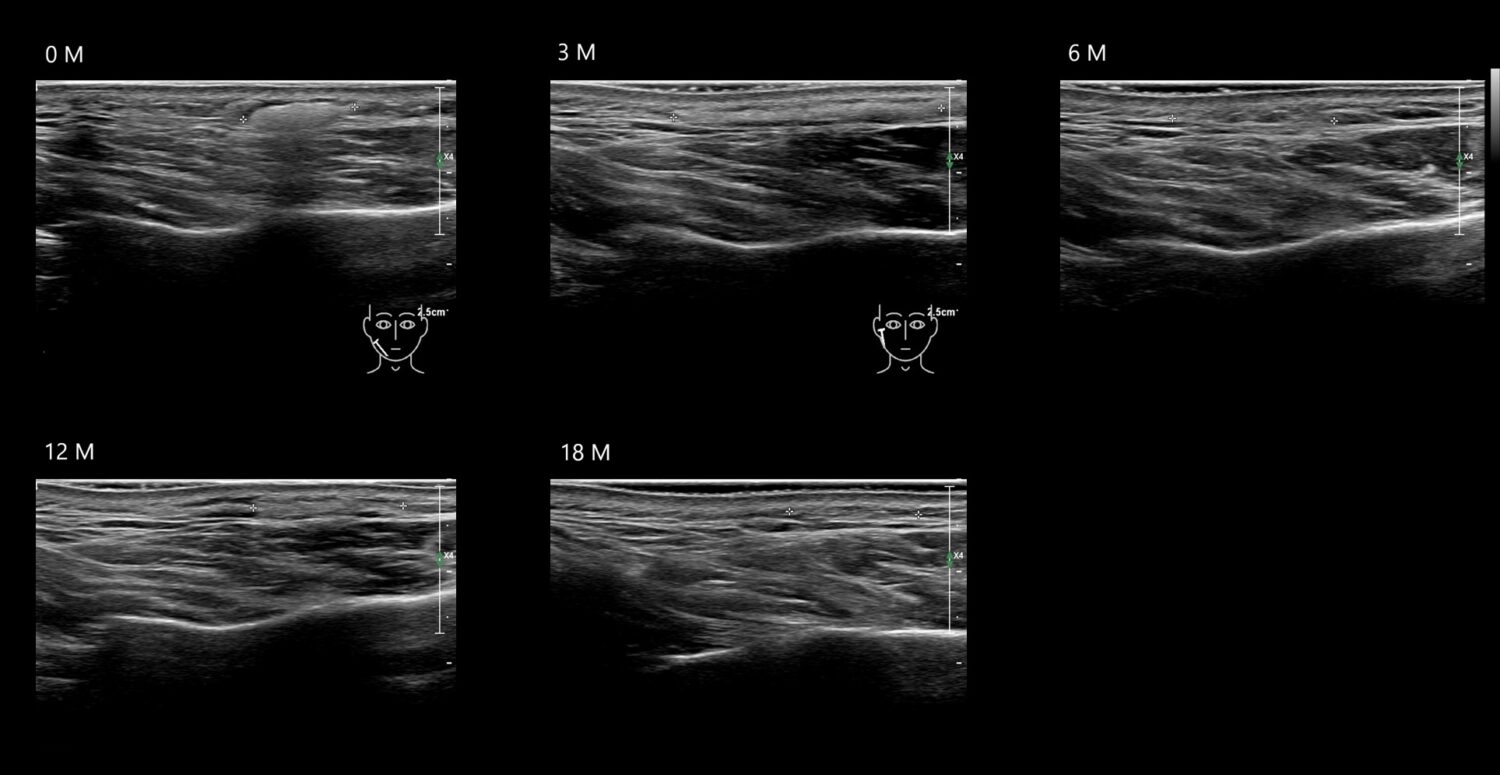

Fillers

Draw in the image on the right where the fillers are located. To check if your answer is correct, please click on the secondary image.